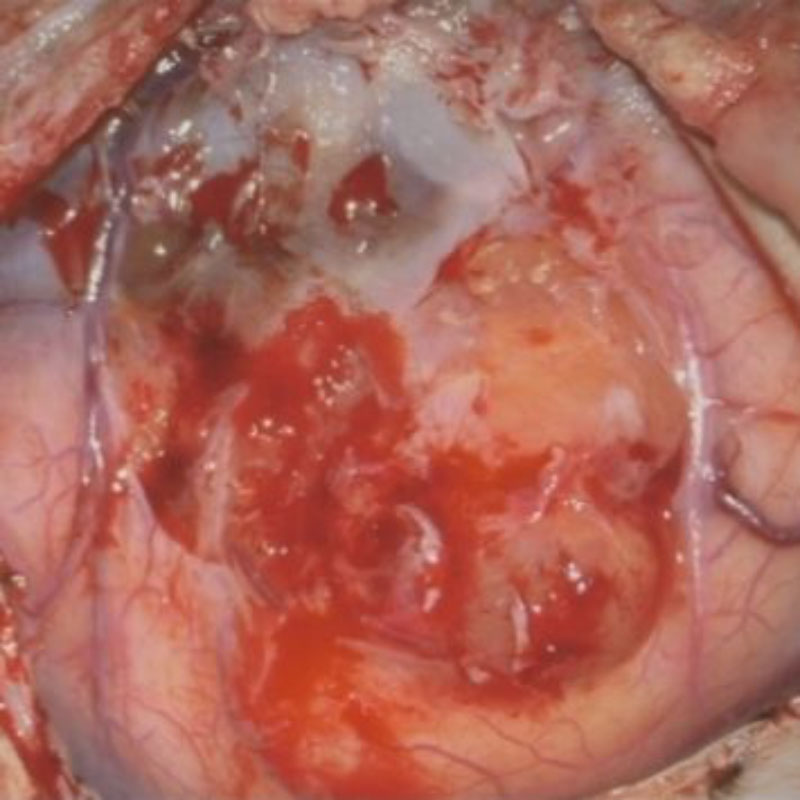

術中写真

摘出 前

摘出 中

摘出 後